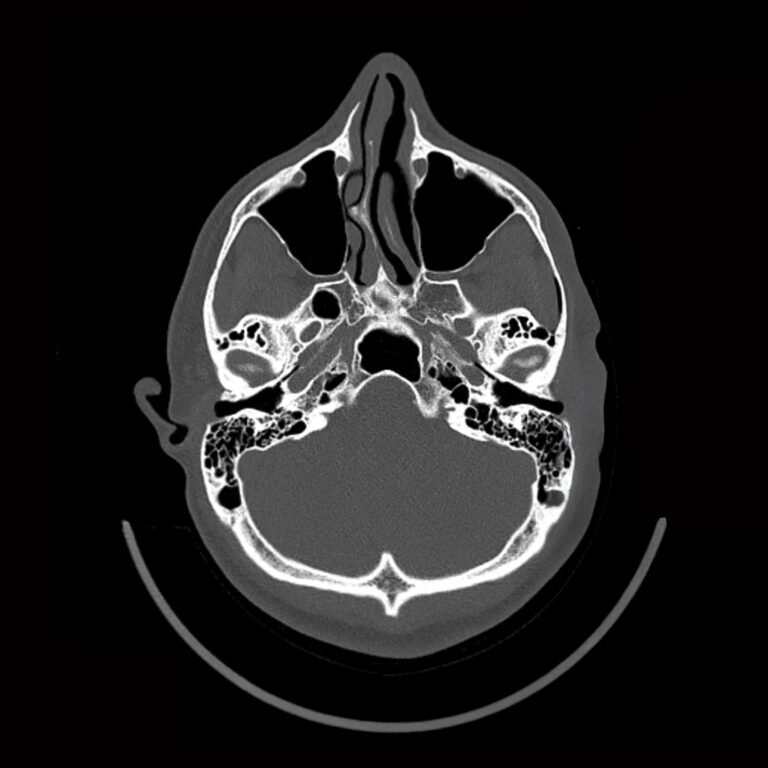

Fractura nasal o de nariz

Es una lesión en los huesos de la nariz causada por un golpe o caída, que puede provocar dolor, sangrado, deformidad y dificultad para respirar.

¿Cómo se trata?

El tratamiento depende del tipo de fractura:

• Reducción cerrada: reposicionamiento manual de los huesos sin cirugía si la lesión es reciente.

• Cirugía: se corrige la estructura nasal cuando la fractura es más compleja o afecta la respiración.